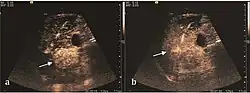

2D ultrasound, Doppler ultrasound and especially CEUS can play an important role in pretherapeutic staging, particularly when sectional imaging investigations (CT, MRI) provide uncertain results or are contraindicated. During the interventional procedure, ultrasound allows guidance of the needle into the tumor. CEUS allows guidance in areas of viable tissue and avoids intratumoral necrotic areas. CEUS also allows assessment of therapeutic effect immediately post-procedure (with the possibility of reintervention in case of partial response) . To accurately assess the effectiveness of treatment it is mandatory to compare the tumor diameter before therapy with the ablation area. The volume of damaged tissue must be higher than the initial tumor volume. CEUS appearance is that of central nonenhanced area showing a peripheral homogeneous hyperenhanced rim due to post-procedure inflammation. 24 hours after the procedure the inflammatory peripheral rim is thinning and the necrotic area appears larger than at the previous examination. Thus, a possible residual tumor may appear more evident. Residual tumor has poorly defined edges, irregular shape, and the tumor diameter is unchanged. Residual tumor tissue is evidenced at the periphery of the tumor as an eccentric area behaving as the original tumor at CEUS examination, with arterial hyperenhancement and portal and late wash-out. Ultrasound examination 24 hours after the procedure, including CEUS, can show apart from the character of the lesion any potential post-intervention complications (e.g. active bleeding).

Local recurrence is defined as recurrence of a hyperenhanced area at tumor periphery in the arterial phase, with portal and late wash-out. Sometimes, especially for HCC treated by alcoholization (PEI) hyperenhanced septa or vessels can be shown inside the lesion.